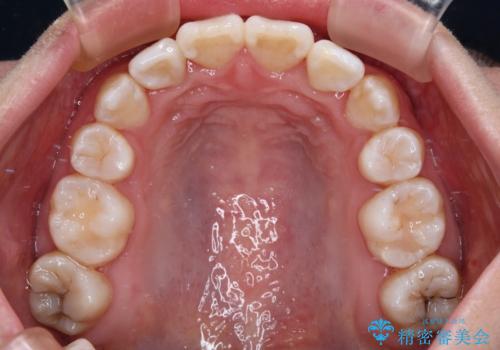

- 飛び出した上顎の前歯と八重歯を気にして来院された患者様です。

口元を積極的に引っ込めるために、上下左右の小臼歯計4本を抜歯することとしました。